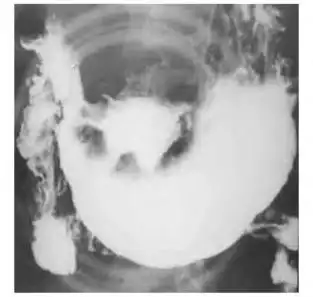

关键词 环堤征

溃疡型:龛影大多成多角形;周围有清楚的环堤;周围皱襞中断,末段呈杵状

图3-41 胃溃疡型癌,钡餐检查,见腔外不规则龛影,有"环堤"及"指压迹"征